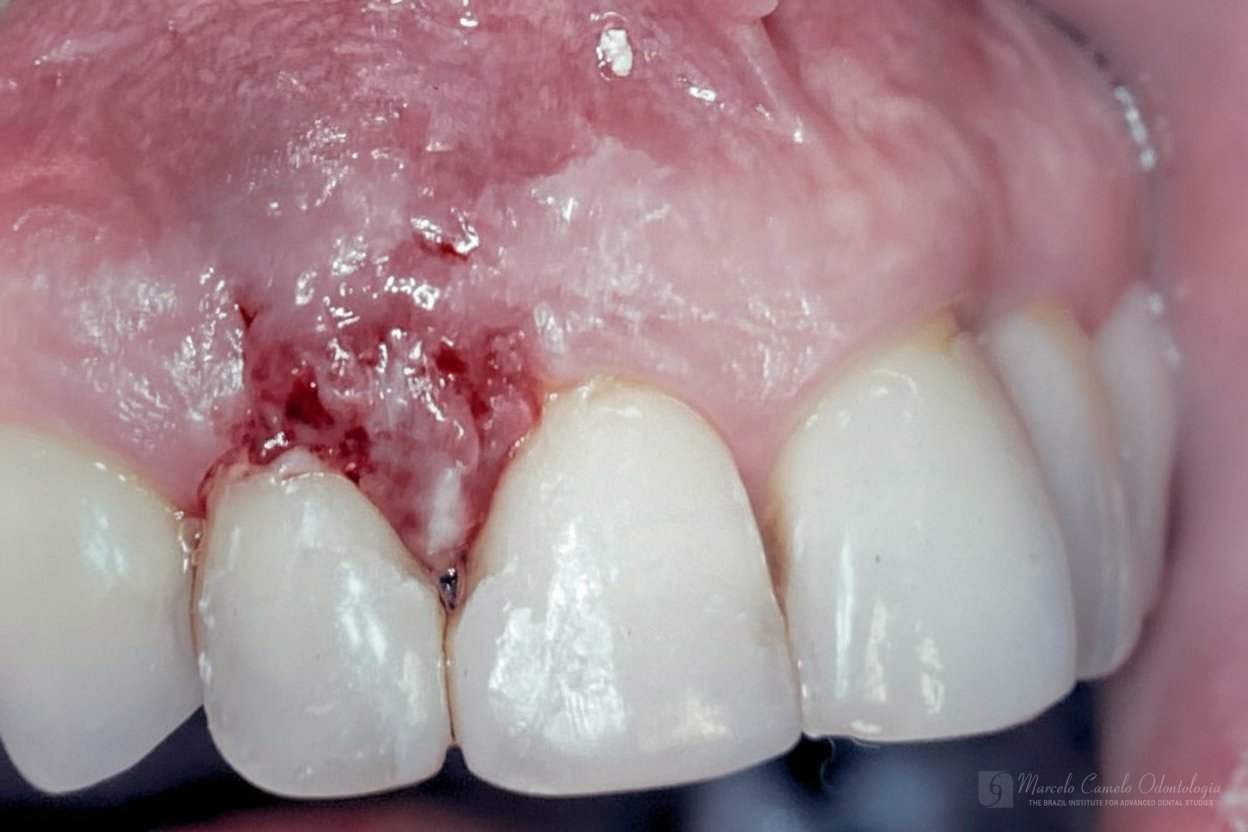

Para casos com boa qualidade de mucosa queratinizada, um envelope vestibular recebe a porção desepitelizada do enxerto pediculado.